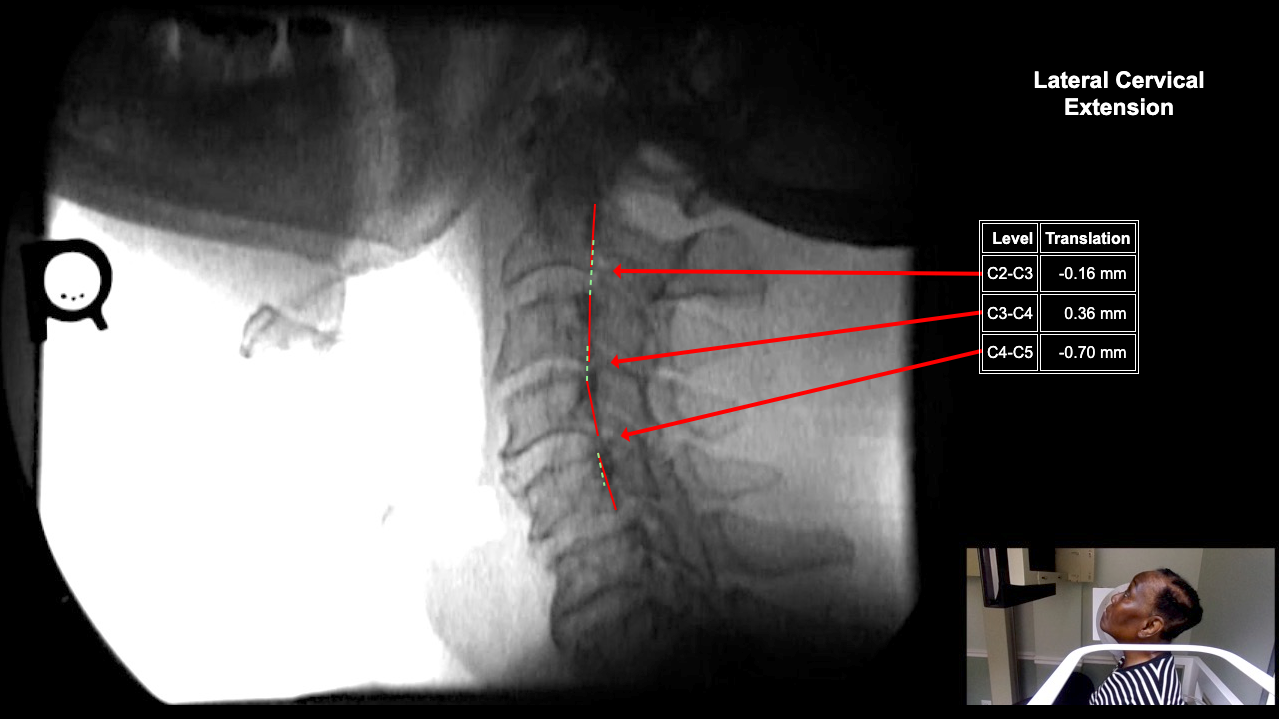

Calibrate Image